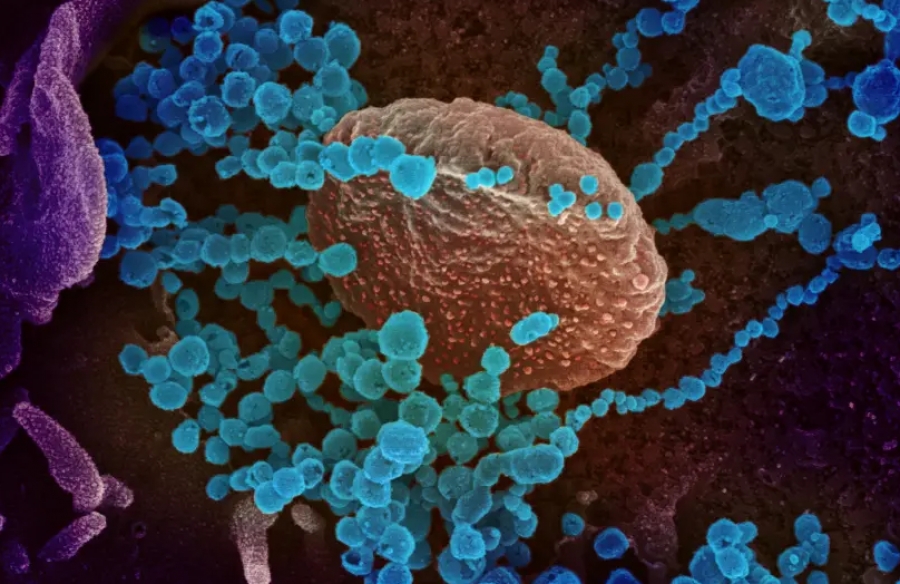

Η καινοτόμος θεραπεία κατά του covid 19 βάζει φραγμό στο σημείο εισόδου του ιού στο κύτταρο

Το

νέο φάρμακο εμποδίζει το σημείο εισόδου του κορωνοϊού στο κύτταρο χωρίς

να βλάψει την ενζυματική λειτουργία του σημείου εισόδου.

Μια

καινοτόμος θεραπεία για τον COVID-19 χρησιμοποιεί ένα μοριακό «σούπερ

φελλό» για να μπλοκάρει το σημείο εισόδου που χρησιμοποιείται από τον ιό

SARS-CoV-2 για να εισέλθει στο κύτταρο, παρακάμπτοντας ζητήματα που θα

μπορούσαν να προκύψουν με άλλες θεραπείες που στοχεύουν σε ακίδα

πρωτεΐνης στον ιό, ανέφερε το Ινστιτούτο Επιστήμης Weizmann.

Οι περισσότερες θεραπείες και εμβόλια

για τον SARS-CoV-2 στοχεύουν την ακίδα πρωτεΐνης στο εξωτερικό

περίβλημα του ιού, αλλά αυτή η πρωτεΐνη θα μπορούσε να μεταλλαχθεί

επηρεάζοντας αρνητικά την αποτελεσματικότητα τέτοιων θεραπειών.

Οι

ερευνητές του Weizmann αποφάσισαν να ακολουθήσουν μια διαφορετική

προσέγγιση, στοχεύοντας στους υποδοχείς του μετατρεπτικού ενζύμου 2 της

αγγειοτενσίνης (ACE2) μέσω των οποίων ο ιός εισέρχεται στο κύτταρο.